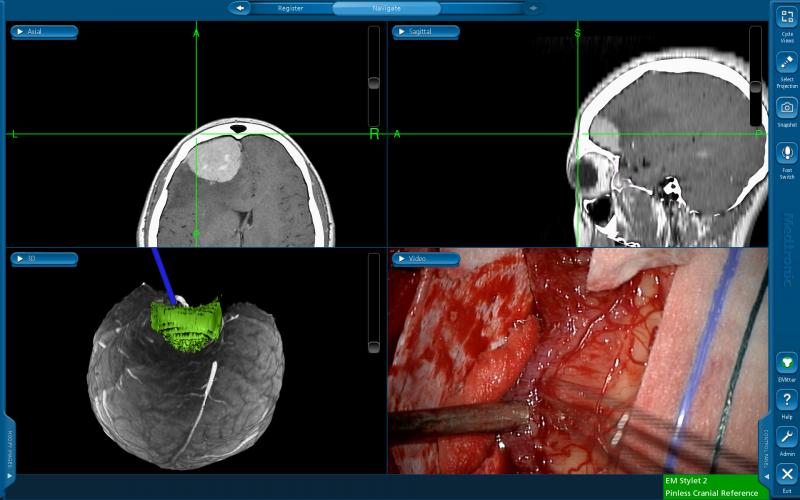

Los tumores dentro del cerebro se dividen de acuerdo a la célula cerebral que lo originó. Adicionalmente utilizamos tecnología de punta como el sistema de neuronavegación (GPS del cerebro).